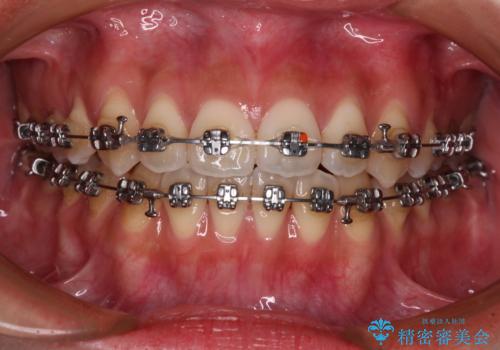

受け口と開咬を急速拡大装置とワイヤー装置で改善

- メタルブラケット

- 1年3ヶ月